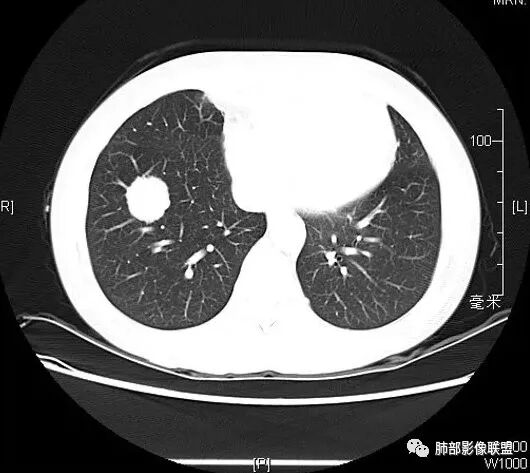

双肺多发大小不等结节,以胸膜下为主,部分边缘平直,彭隆,整体较密实,临床无症状体检发现,考虑淋巴瘤,转移瘤,IMT.

老年男性,发现占位半年,双肺多发结节,病灶边界清晰,浅分叶,部分支气管进入后堵塞,部分病灶内部密实,无增强,考虑真菌感染,淋巴瘤待排除。

双肺多发结节肿块,部分位于胸膜下,部分结节内可见扩张支气管,右肺上叶近肺门处结节呈分叶毛刺,支气管阻塞、扭曲扩张,考虑1淋巴瘤2腺癌转移。

双肺多发结节,密度均匀,部分可见支气管进去后堵塞,有胃部手术史,考虑淋巴瘤?鉴别腺癌转移,其他?

脾大表现,两肺叶多发结节,部分呈肿块(浅分叶轮廊),实性密度,边缘清楚,有膨隆,近胸膜下分布,支气管僵直略扩张,一元论,首选淋巴瘤。

双肺多发结节肿块,胸膜下支气管树旁为主,部分内可见支气管穿行,支气管扩张。淋巴瘤?肉芽肿性多血管炎?鉴别转移

必有路:老年男性,两肺多发结节,团块,病灶都位于胸膜下,血管相关,有支气管充气征,分叶,无坏死,周围无晕疾病谱:隐球菌病,GPA,OP,malt,转移,IgG4相关,栓塞诊断:鉴于患者体检发现半年,症状逍遥重点考虑 淋巴瘤 可能鉴别:隐球菌病,GPA,IgG4相关,转移

多发团块影,胸膜下为主,边缘清楚、膨隆、平直,部分病灶可见分叶,病灶内支气管穿行,血管穿行,考虑淋巴瘤。

刚看了视频,老年男性,体检发现,30年前有胃部手术史。双肺野多发结节肿块影,沿支气管血管束或胸膜下分布,有的结节内似有小空洞,支气管进入走形自然,肿块边缘膨隆,有分叶,支气管进入后有的截断,大部分支气管穿过,走形自然,纵隔内未见明显肿大淋巴结,总体考虑淋巴瘤,炎性肉芽肿(肉芽肿血管炎或隐球菌肺炎)等。考虑后者可能性大,肉芽肿血管炎或隐球菌肺炎,鉴别淋巴瘤。

病变分布特点,胸膜下,叶间胸膜下为主,呈大小不等结节级团块影,部分病灶内见支气管影,病灶收缩不明显,从分布及慢性发病看,隐球和淋巴瘤都可,补充增强,病灶内见血管穿行,强化不明显,支持淋巴瘤

老年男性,两肺多发结节肿块,胸膜下分布为主,部分支气管进入闭塞,增强扫描有强化,血管穿行无破坏,边缘尚光滑,周围无晕,病灶整体膨隆为主,半年病程,症状逍遥,首先考虑淋巴瘤

棉花糖:双肺多大小不等结节,边缘清楚,无毛刺,浅分叶,胸膜下分布为主,内可见支气管穿行,增强后中等程度强化,病灶内血管走行自然,考虑淋巴瘤,鉴别GPA